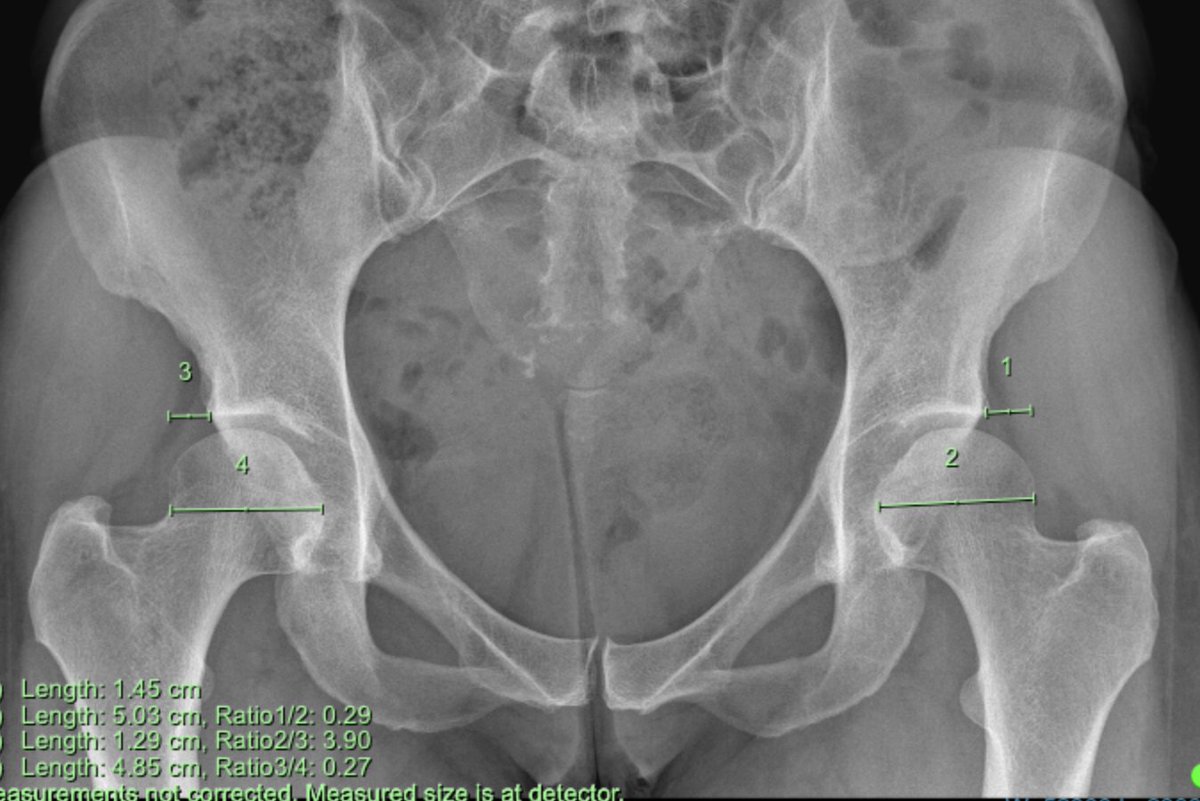

#CaseOfTheWeek‼️🥳‼️ ☢️🩻☠️Case#22☠️🩻☢️ #Mass 📲➡️➡️#Diagnosis❔❓❔ #FOAMRad #RadEd #MedEd #OrthoEd #OrthoTwitter @ssr_rwg @UWRadRes @ISSVA_org